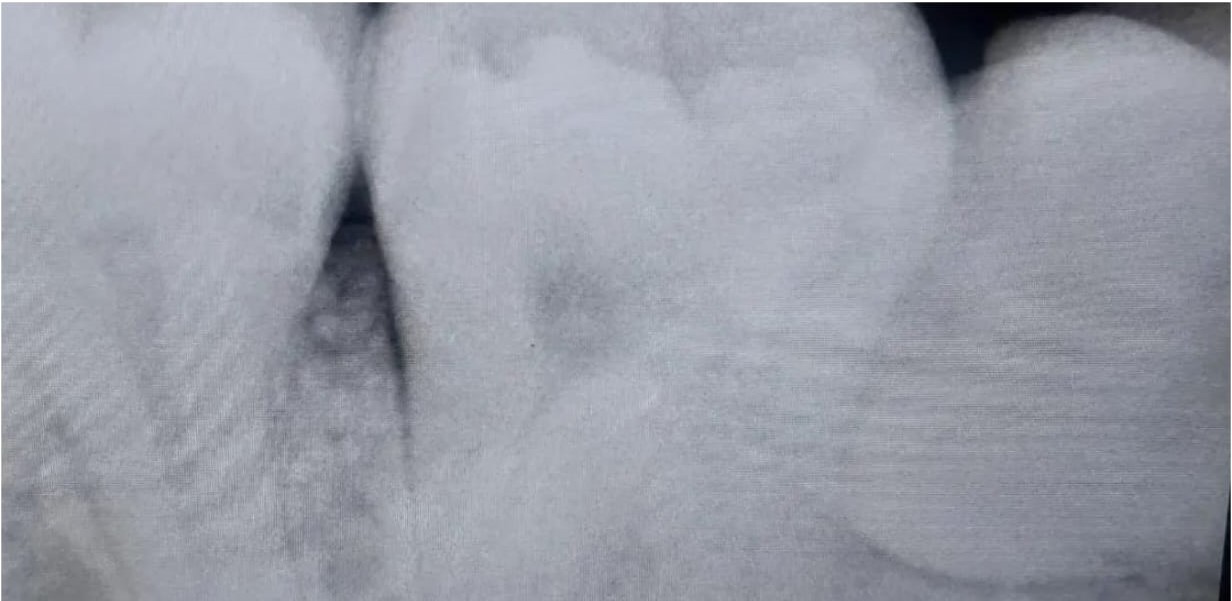

If you experience pain, swelling, infection, or misalignment, your dentist may recommend extraction. X-rays help assess if removal is necessary.